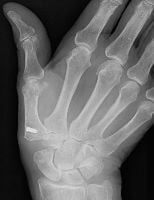

マレット変形

スワンネック変形

末節骨裂離骨折の経皮ピンニング

槌指とは木槌(マレット)のように変形した指を指す言葉であり、これには、末節骨の伸筋腱が付着する部位の裂離骨折によっておこるものと、伸筋腱の終止腱の断裂によっておこるものが含まれます。

いずれの場合も、症状はDIP関節の自動伸展障害ですが、放置するとスワンネック変形(白鳥の首様の変形)を生じます。さらに、骨折の場合には早期にDIP関節の変形性関節症を生じる原因となることがあります。

治療は、骨折があれば骨片の整復・固定を行うことで良好な結果が得られます。腱断裂の場合には2ヶ月間の外固定により4割の指に良好な結果が得られますが、6割の指には様々な程度(5〜20°)のDIP関節伸展障害が残存します。結果は、どれだけ早期に固定を開始できたか?と、どれだけしっかりとDIP関節の伸展位固定を維持できたか?にかかっており、ただ単に固定していたら治る、というものではありません。

陳旧例で骨の変形癒合がある場合には、骨切術により変形の矯正が可能です。腱断裂の陳旧例では、手術による腱の縫縮あるいは腱移行術によって変形の矯正が図られます。